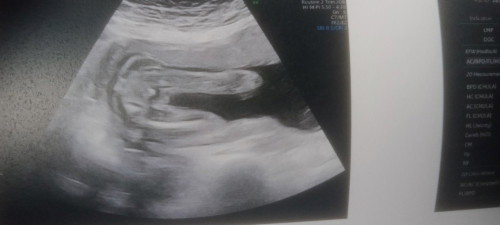

สอบถามคะแม่ว่าผู้หญิงหรือผู้ชายคะคุณหมอบอกน่าจะผู้หญิง

ผู้หญิงหรือผู้ชายคะ

น่าจะหญิงนะคะ